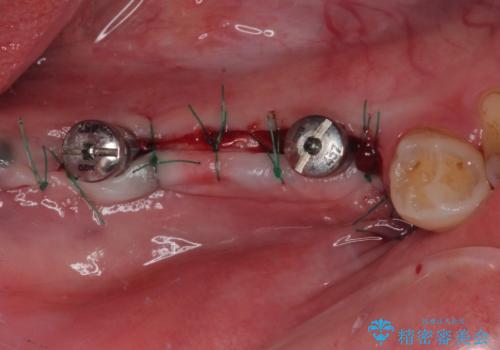

ブリッジの支台歯2本を抜歯し、反対側の咬合負担を軽減するために、通常よりも短い待機時間で2本のインプラントを埋入することとしました。

インプラントは、根管治療をした歯と比べると、破折するリスクは圧倒的に低いですが、こちらの方のように、臼歯しか咬合していない場合、歯ぎしりによる負担でインプラント周辺の骨が吸収する可能性があります。

就寝時のマウスピースの装着と定期的な通院によるレントゲン撮影や咬み合わせのチェックが必須となります。